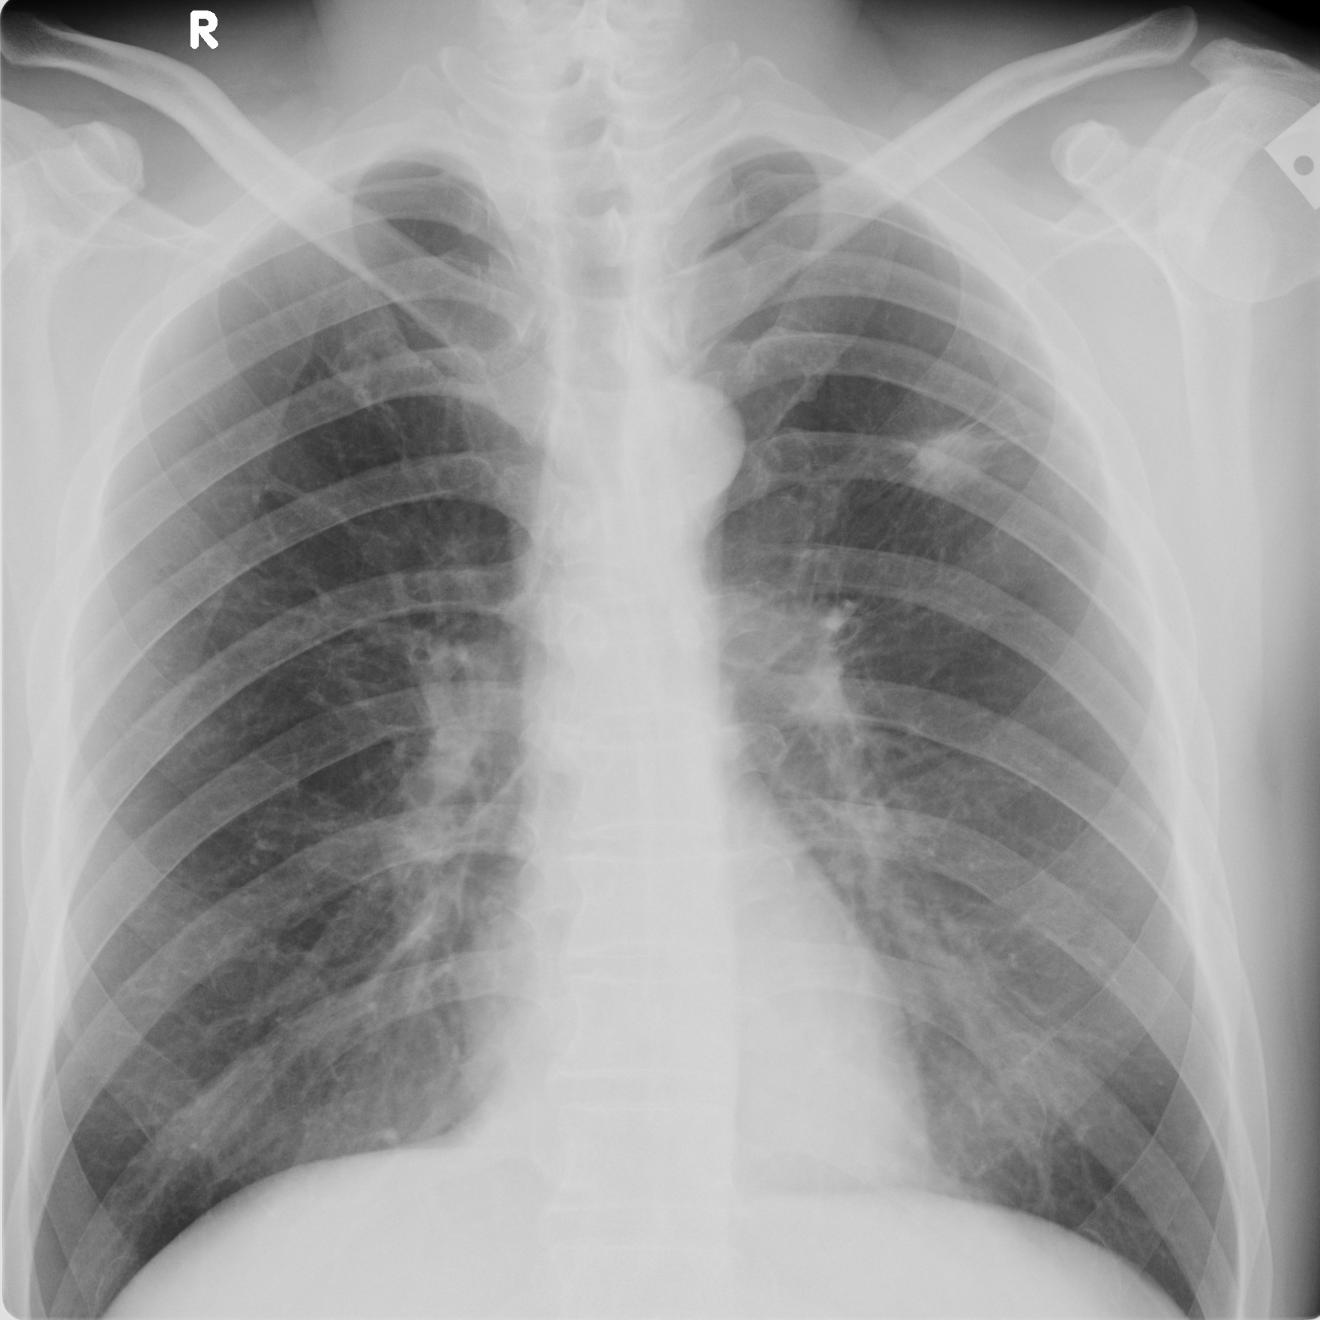

以下是引用zhangzhongshou在2008-5-24 13:39:00的发言:[br]小红右侧大量胸腔积液,右侧中叶台阶征/水平叶裂积液/右上肺纤维灶不除外,建议侧位片,必要时进一步检查。[br]小明:左上肺结核瘤可能性大,请结合临床,必要时建议ct检查。[br][br]影像诊断必须要密切结合临床,建议楼主以后不要上传这样的看图说话。谢谢了!

以下是引用黑白光影在2008-5-24 15:32:00的发言:[br]看图不说话对不起观众,下面开始乱说:[br]老红右侧大量胸腔积液,部分肺膨胀不全。[br]老明左上肺癌可能。